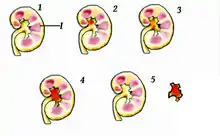

Location

Urolithiasis refers to stones originating anywhere in the urinary system, including the kidneys and bladder.[16] Nephrolithiasis refers to the presence of such stones in the kidneys. Calyceal calculi are aggregations in either the minor or major calyx, parts of the kidney that pass urine into the ureter (the tube connecting the kidneys to the urinary bladder). The condition is called ureterolithiasis when a calculus is located in the ureter. Stones may also form or pass into the bladder, a condition referred to as bladder stones.[83]

Size

Stones less than 5 mm (0.2 in) in diameter pass spontaneously in up to 98% of cases, while those measuring 5 to 10 mm (0.2 to 0.4 in) in diameter pass spontaneously in less than 53% of cases.[84]

Stones that are large enough to fill out the renal calyces are called staghorn stones and are composed of struvite in a vast majority of cases, which forms only in the presence of urease-forming bacteria. Other forms that can possibly grow to become staghorn stones are those composed of cystine, calcium oxalate monohydrate, and uric acid.[85]